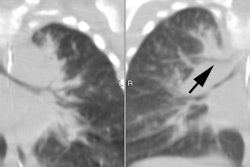

Unsuspected congenital diaphragmatic hernia: The newborn shown below presented with respiratory difficulty, but did not have a scaphoid abdomen. The frontal CXR demonstrated and abnormal lucency and curvilinear density in the left base. A lateral view revealed findings concerning for a diaphragmatic hernia. This was confirmed on CT imaging- note that a portion of the stomach and the spleen have herniated through the defect. |